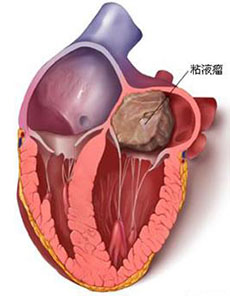

心脏瓣膜病及其他疾病

疾病介绍:心脏瓣膜病及其他疾病心脏瓣膜病就是指二尖瓣、三尖瓣、主动脉瓣和肺动脉瓣的瓣膜因风湿热、黏液变性、退行性改变、先天性畸形、缺血性坏死、感染或创…【详细】

心脏瓣膜病及其他疾病

疾病介绍:心脏瓣膜病及其他疾病心脏瓣膜病就是指二尖瓣、三尖瓣、主动脉瓣和肺动脉瓣的瓣膜因风湿热、黏液变性、退行性改变、先天性畸形、缺血性坏死、感染或创…【详细】

心脏瓣膜病及其他疾病

疾病介绍:心脏瓣膜病及其他疾病心脏瓣膜病就是指二尖瓣、三尖瓣、主动脉瓣和肺动脉瓣的瓣膜因风湿热、黏液变性、退行性改变、先天性畸形、缺血性坏死、感染或创…【详细】

心脏瓣膜病及其他疾病

疾病介绍:心脏瓣膜病及其他疾病心脏瓣膜病就是指二尖瓣、三尖瓣、主动脉瓣和肺动脉瓣的瓣膜因风湿热、黏液变性、退行性改变、先天性畸形、缺血性坏死、感染或创…【详细】

心脏瓣膜病及其他疾病

疾病介绍:心脏瓣膜病及其他疾病心脏瓣膜病就是指二尖瓣、三尖瓣、主动脉瓣和肺动脉瓣的瓣膜因风湿热、黏液变性、退行性改变、先天性畸形、缺血性坏死、感染或创…【详细】

心脏瓣膜病及其他疾病

疾病介绍:心脏瓣膜病及其他疾病心脏瓣膜病就是指二尖瓣、三尖瓣、主动脉瓣和肺动脉瓣的瓣膜因风湿热、黏液变性、退行性改变、先天性畸形、缺血性坏死、感染或创…【详细】

心脏瓣膜病及其他疾病

疾病介绍:心脏瓣膜病及其他疾病心脏瓣膜病就是指二尖瓣、三尖瓣、主动脉瓣和肺动脉瓣的瓣膜因风湿热、黏液变性、退行性改变、先天性畸形、缺血性坏死、感染或创…【详细】